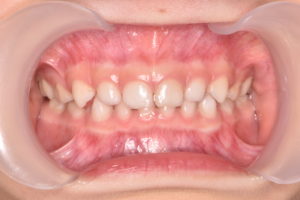

受傷直後

年齢:3歳女の子

30分前にこけて上の前歯を強打し、この写真からはわかりませんが、上の前歯の位置異常(脱臼)が生じています。

参考症例 外傷により右上前歯の脱臼が生じています

乳歯の形態には異常はなく、打った歯の位置が変わっているため元の位置に整復し、ワイヤーで固定を行います。

脱臼した左上乳中切歯を整復し、両隣の歯とワイヤーで固定します。

脱臼した歯は一度骨から剥がれているため、周囲の骨とくっつくまでこの状態で経過観察をしていきます。